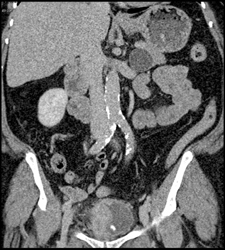

Bladder Cancer